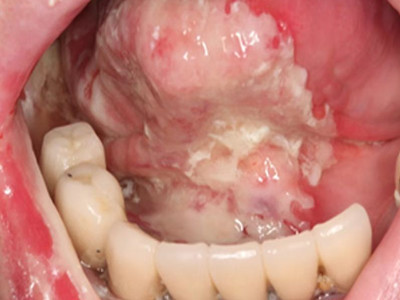

牙龈癌多源于牙间乳头及龈缘区,溃疡呈表浅、淡红,以后可出现增生。由于黏骨膜与牙槽突附着甚紧,较易早期侵犯牙槽突骨膜及骨质,进而出现牙松动,并可发生脱落。X线片可出现恶性肿瘤的破坏特征虫蚀状不规则吸收。

牙龈癌常发生继发感染,肿瘤伴以坏死组织,触之易出血。体积过大时可出现面部肿胀,浸润皮肤。

即使是早期的牙龈癌,原则上均应行牙槽突切除,而不仅仅是牙龈切除术。较晚期的应作下颌骨或上颌骨次全切除术。牙龈癌已侵入上颌窦者,应行全上颌骨切除术。一旦发生转移,即应行治疗性颈淋巴清扫术。